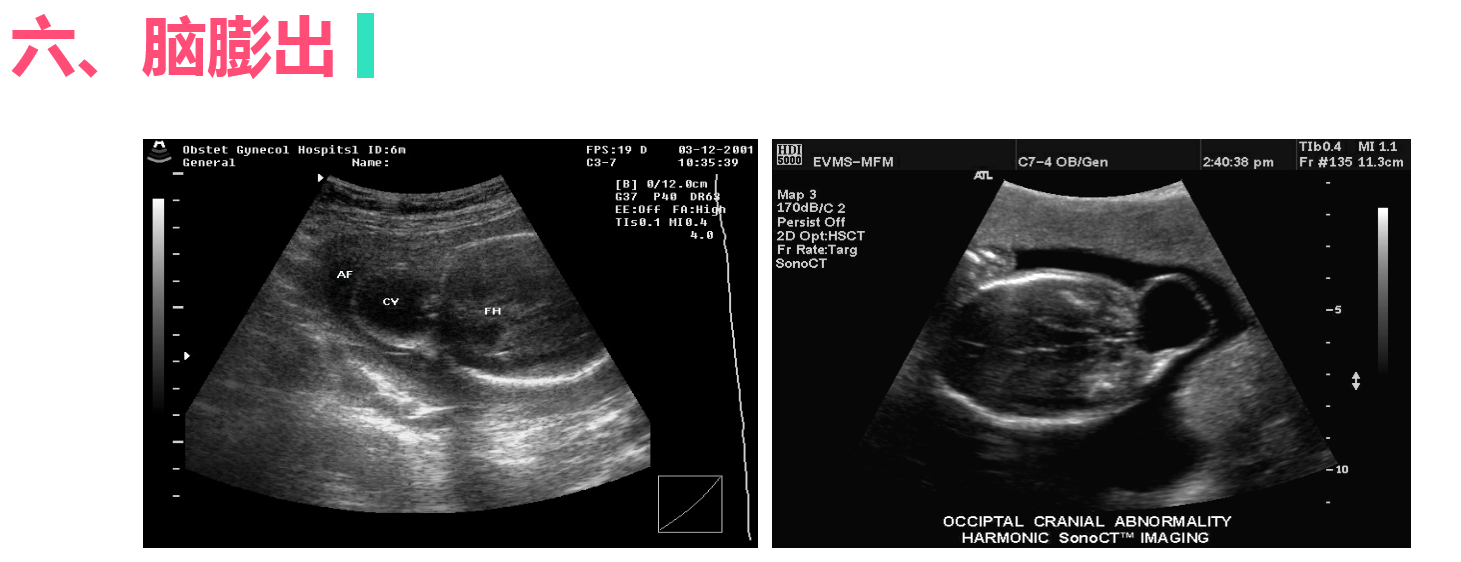

胎儿先天性畸形的超声诊断

• 4.6 胎儿先天性畸形的超声诊断